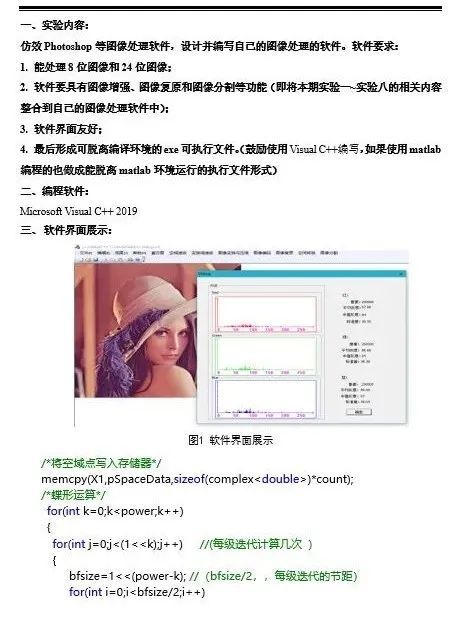

实验室留校学生正在进行科研工作

一位2018级188博金宝亚洲体育的本科生这样评价林江莉教授开设的《生物医学图像处理》课程:“林老师注重对我们实践能力、理论与应用的融合贯通能力的培养,老师在布置作业的时候会让我们从源头去编程,以实现各种图像处理的算法并学习如何验证理论。”

学生展示的《生物医学图像处理》部分实验报告